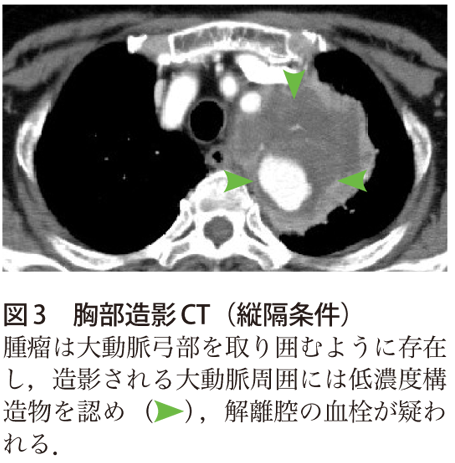

解答 解説 喀血 胸痛を主訴に紹介受診した70歳代女性 実践 画像診断q A 羊土社 レジデントノート 実践 画像診断q A 羊土社 レジデントノート 羊土社